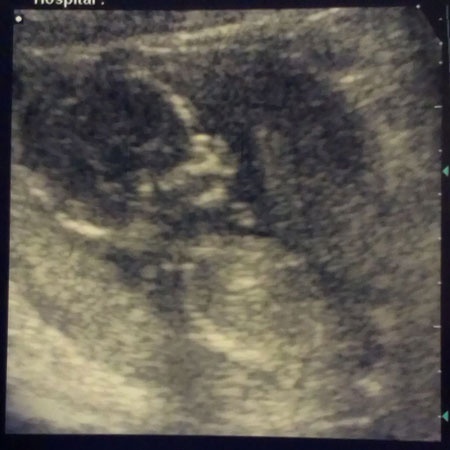

A kérdések után meglestük Babácskát, és hát úgy tűnik, a kis drága szégyenlős, pedig próbáltuk normál ultrahanggal, majd hüvelyi ultrahanggal, de erősen szorítja a combjait.

Nem baj, majd legközelebb – vagy azután - kiderül, de hogy ilyen alaposan meglestük, az azért megnyugtató, hiszen minden rendben. Békám 16 hetesen 14 centiméter és 130 gramm, mikor a naplót olvassátok már 16+5 a napok száma.